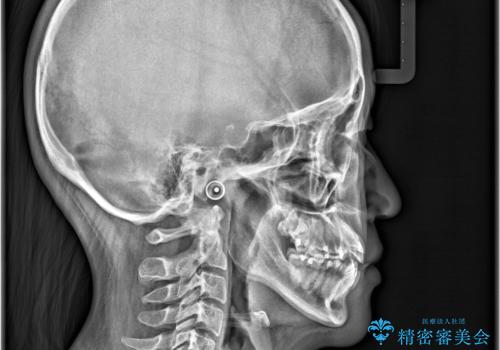

- 「歯のでこぼこを治したい」を主訴に来院された患者様です。 上下ともに、歯のでこぼこが強く、上下左右4の抜歯をし、ワイヤー矯正で治療を行いました。

叢生量がかなり多かったのですが、歯肉退縮も失活歯も無くとても綺麗な歯並びになりました。

歯のでこぼこは、歯周病や虫歯のリスクも、とても高いので、見た目のみならず、将来の歯の寿命自体もかなり伸ばす事が出来た治療でした。